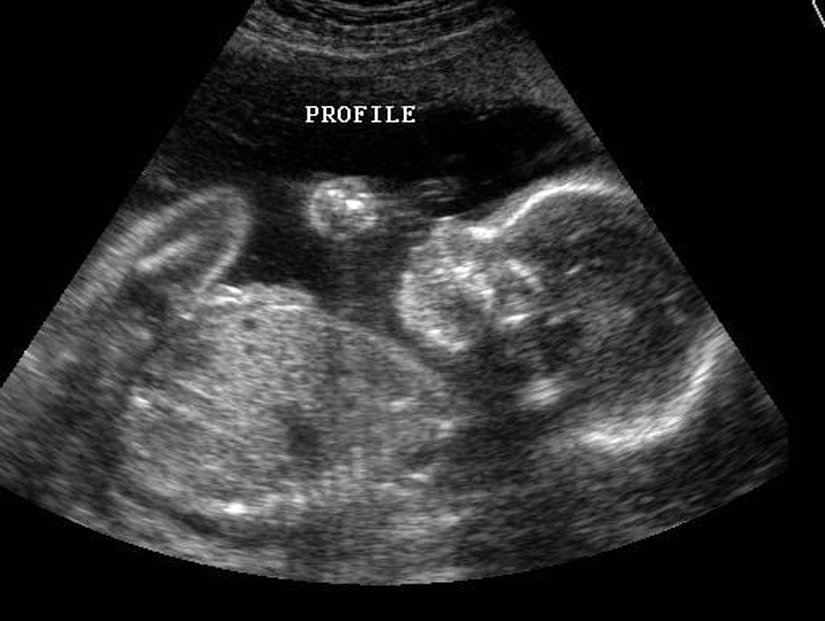

Genellikle ebeveynler, yavrularının ilk fotoğraflarını oldukça bulanık ve çoğu zaman pek bir şey anlaşılmaz bir şekilde alırlar. Çünkü ultrason teknolojileri sadece siyah-beyaz ve oldukça fazla gürültülü (alınmak istenen sonucu etkileyen sinyalli) sonuçlar verir. Tipik bir örneği şöyledir:

2 boyutlu ultrason görüntülerinde, duyabileceğimiz frekansın üzerindeki ses dalgaları gönderen bir çubuk, karna veya vajina içerisine konularak vücudu bu ses dalgalarıyla tarar. Bebeğin vücudundan ve annenin iç organlarından farklı şekillerde yansıyan ses dalgaları, sonradan bilgisayar yardımıyla fotoğrafa dönüştürülür ve böylece bebeğin bir kesiti oluşturulur. Doppler fetal ultrason yöntemindeyse, benzer bir ultrason cihazı kullanılarak bebeğin kalp atışları da tespit edilir ve yine bir bilgisayar yardımıyla bu sinyaller güçlendirilerek, annenin ve hekimin işitebileceği düzeye yükseltilir.

Aşağıda gördüğünüz, iki sıra bebek fotoğrafı. Bu fotoğrafları özel kılan şey, 4 boyutlu ultrason (3 boyutlu çekim + zaman) yöntemiyle kaydedilmiş olmaları. Ancak sadece bu da değil... Üstteki sıra, annesi sigara içen bir fetüse ait. Alttaki ise içmeyene...

İlk etapta çok fark görülemeyebilir. Ancak fotoğraf serisini soldan sağa doğru dikkatle takip edecek olursanız, üstteki bebeğin ağzını yüzünü hareket ettirdiğini ve eliyle yüzüne dokunmaya çalıştığını göreceksiniz. Alttakinin yüzü ise normal bir şekilde durmaktadır ve elleriyle yüzüne dokunma çabası yoktur.

"Ee, ne var bunda?" diyebilirsiniz... Sorun şu ki, bebekler hamileliğin erken evrelerinde yüzlerini buruşturmaya ve elleriyle yüzlerine dokunmaya meyillidirler. Bu normaldir. Ancak hamilelik süresi ilerledikçe, bu davranışlar giderek azalır ve bebek daha ziyade kollarına bacaklarına ve vücudunun geri kalanına dokunarak özellikle uzuvlarını tanımaya çalışır. Bunun nedeni, sinir sistemi ve beyni geliştikçe, uzuvlarını daha aktif olarak kullanmaya başlamasıdır. Yüzüne olan ilgisi azalır. Dahası, yüzünü de buruşturmayı bırakır.

Fakat Durham Üniversitesi tarafından yapılan yeni bir araştırmada, hamilelikte sigara içen annelerin yavrularında bu gelişim evrelerinin yavaşladığı gözlendi.[1] Yani üstteki seride, bebek aslında artık bırakmış olmasına rağmen yüzünü buruşturmaya devam ediyor ve yüzüne dokunmaya çalışıyor. Alttaki seride (sigara içmeyen anneni bebeği) ise normal gelişim görülüyor. Uzmanlar bu farklılığı sigaranın sinir sisteminin gelişimi üzerindeki yavaşlatıcı ve olumsuz etkiye bağlıyor.